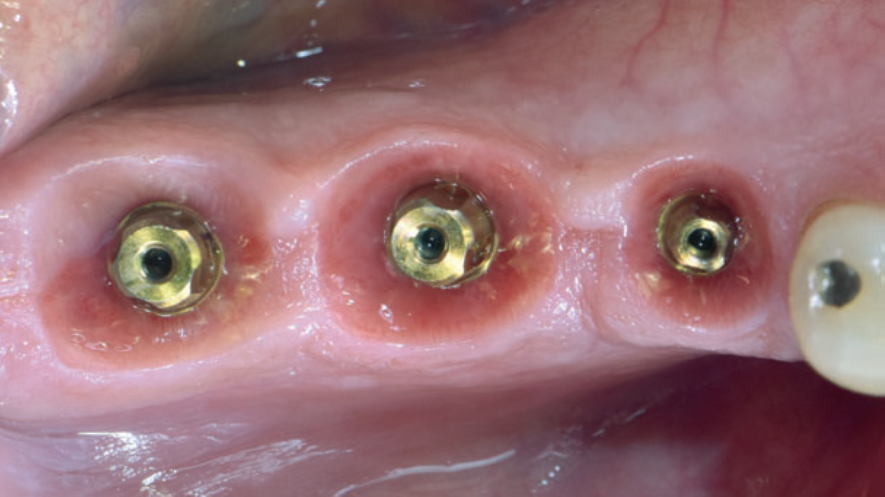

A restauração protética esteticamente agradável de um implante requer a criação de um adequado perfil de emergência da mucosa peri-implantar, que é a transição entre o implante e a coroa protética. Quando corretamente explorado, proporciona uma suave transição da plataforma circular do implante para a anatomia natural do dente. Quanto mais detalhados forem estes processos, maiores serão as chances de sucesso dos tratamentos protéticos reabilitadores.

Ao serem instalados, os implantes que atingem um torque de inserção ≥ 32 Ncm podem ser imediatamente carregados com coroas unitárias de transição não oclusivas. Abaixo deste torque, ou em situações onde não desejamos correr riscos, em vez de uma coroa de transição, instala-se um cicatrizador personalizado contendo um perfil transmucoso com as mesmas características que a coroa provisória teria. Os objetivos dos cicatrizadores customizados nos casos de instalação do implante imediatamente após a exodontia são: selar o sítio cirúrgico respeitando o perfil do alvéolo de extração, estabilizar o coágulo sanguíneo e favorecer a regeneração óssea com o material substituto, evitar o colapso de tecidos moles durante o período de cicatrização e desenvolver um perfil de emergência protético ideal para a futura coroa sobre implante, baseado na anatomia do dente natural extraído, sem receber carga oclusiva.

Nos casos de instalação de implantes em regiões edêntulas, também é possível empregar cicatrizadores personalizados, desenvolvendo um perfil de emergência protético ideal para a futura coroa sobre implante, baseado na anatomia do dente natural ausente. Os dois procedimentos restabelecerão o perfil de emergência original do paciente durante a fase de cicatrização/osseointegração dos implantes, devolvendo a harmonia dentogengival, com a recuperação das papilas interdentais e a reconstituição do arco gengival côncavo, com altura adequada da margem em relação aos dentes adjacentes.